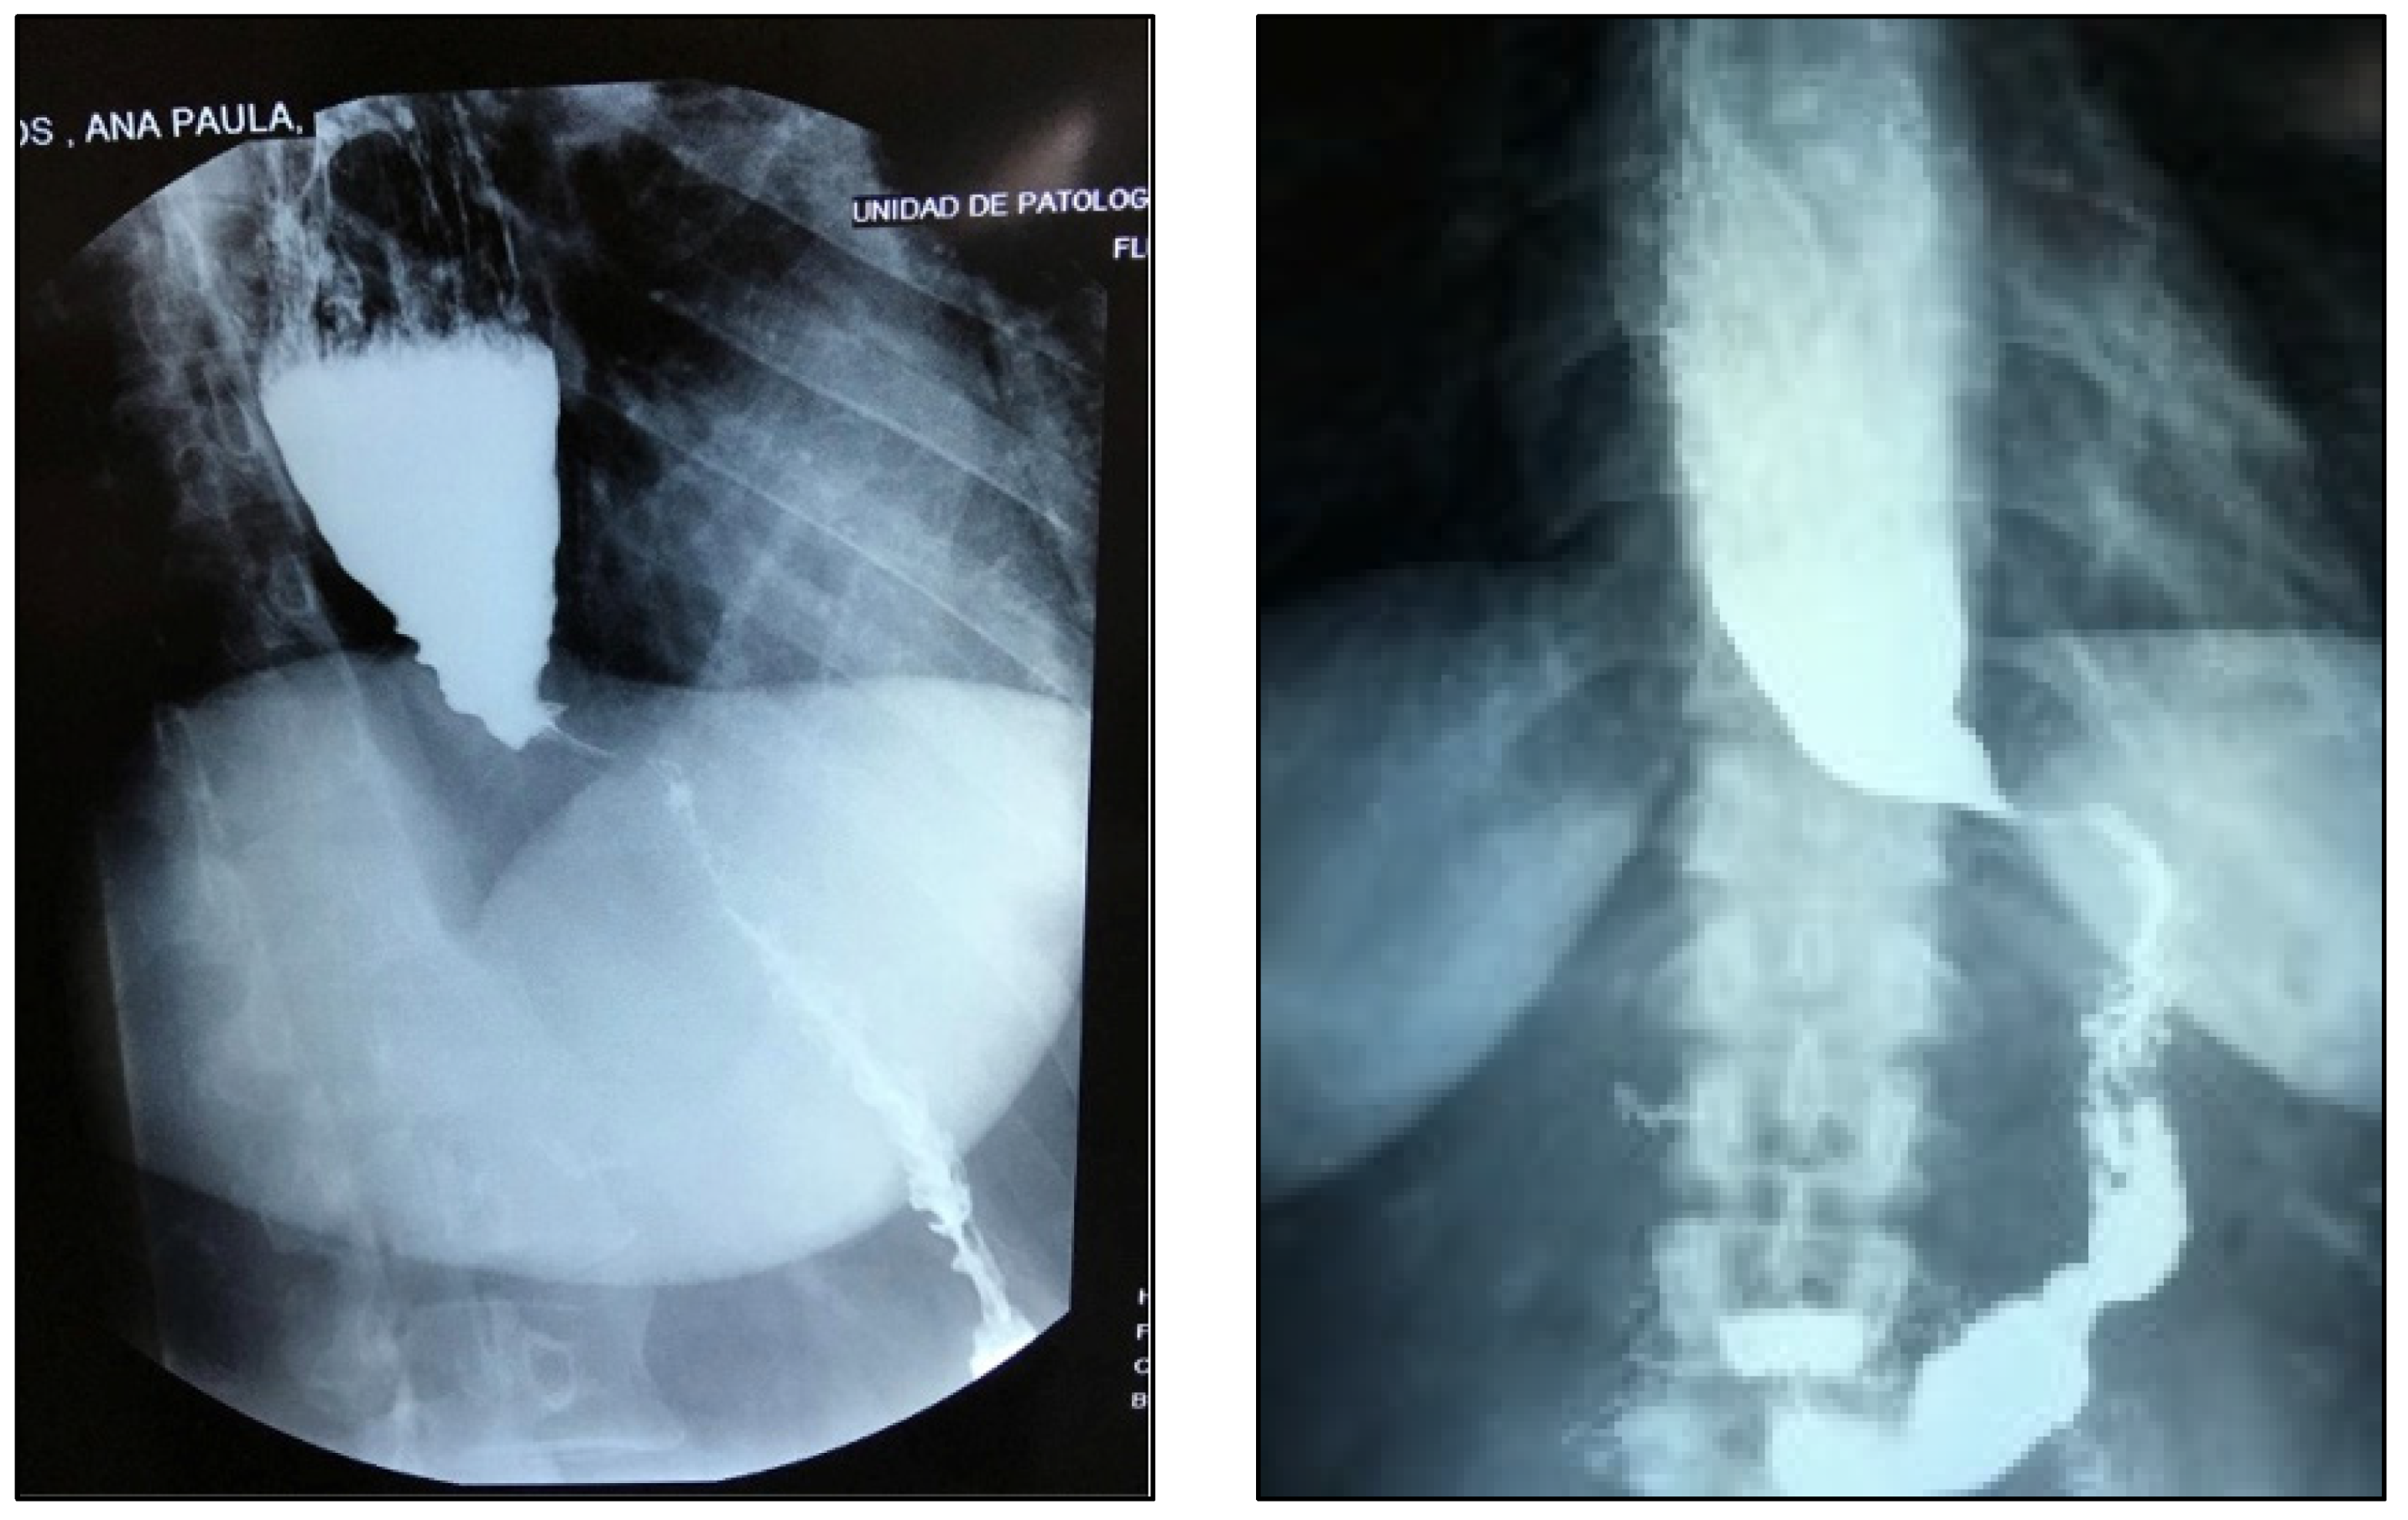

First, a pandendoscopy was performed (Figure 1A,B), showing an increase in the esophageal diameter in its 3 thirds with abundant food debris. A retentive esophagus with a diagnostic impression of probable achalasia was reported. Afterwards, manometry was indicated, identifying a mean residual pressure in the lower esophageal sphincter of 29.1 mmHg. Regarding the upper esophageal sphincter, a mean basal pressure of 133.9 mmHg was reported, with a relaxation time of 1,092ms and a recovery time of 849 ms, compatible with a diagnosis of achalasia subtype II of the Chicago classification ver 3.0 (Figure 2). Finally, an esophagogastroduodenal series was performed (Figure 3A,B) where typical pencil-point images are found. She was scheduled by the surgical service for the performance of a Heller cardiomyotomy with laparoscopic Roux-en-Y Bypass, choosing this technique instead of fundoplication due to the surgical history of gastric sleeve.

Figure 3. A and 3B. Esophageal dilatation, and pencil-point termination of the gastroesophageal junction.